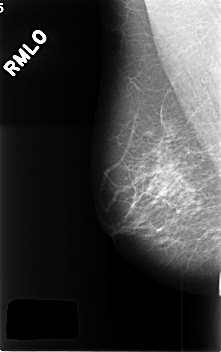

ics_version 1.0 filename C-0360-1 DATE_OF_STUDY 15 5 1997 PATIENT_AGE 59 FILM FILM_TYPE REGULAR DENSITY 2 DATE_DIGITIZED 12 11 1998 DIGITIZER LUMISYS LASER SEQUENCE LEFT_CC LINES 4576 PIXELS_PER_LINE 2896 BITS_PER_PIXEL 12 RESOLUTION 50 OVERLAY LEFT_MLO LINES 4456 PIXELS_PER_LINE 2896 BITS_PER_PIXEL 12 RESOLUTION 50 OVERLAY RIGHT_CC LINES 4560 PIXELS_PER_LINE 2920 BITS_PER_PIXEL 12 RESOLUTION 50 NON_OVERLAY RIGHT_MLO LINES 4576 PIXELS_PER_LINE 2864 BITS_PER_PIXEL 12 RESOLUTION 50 NON_OVERLAY |